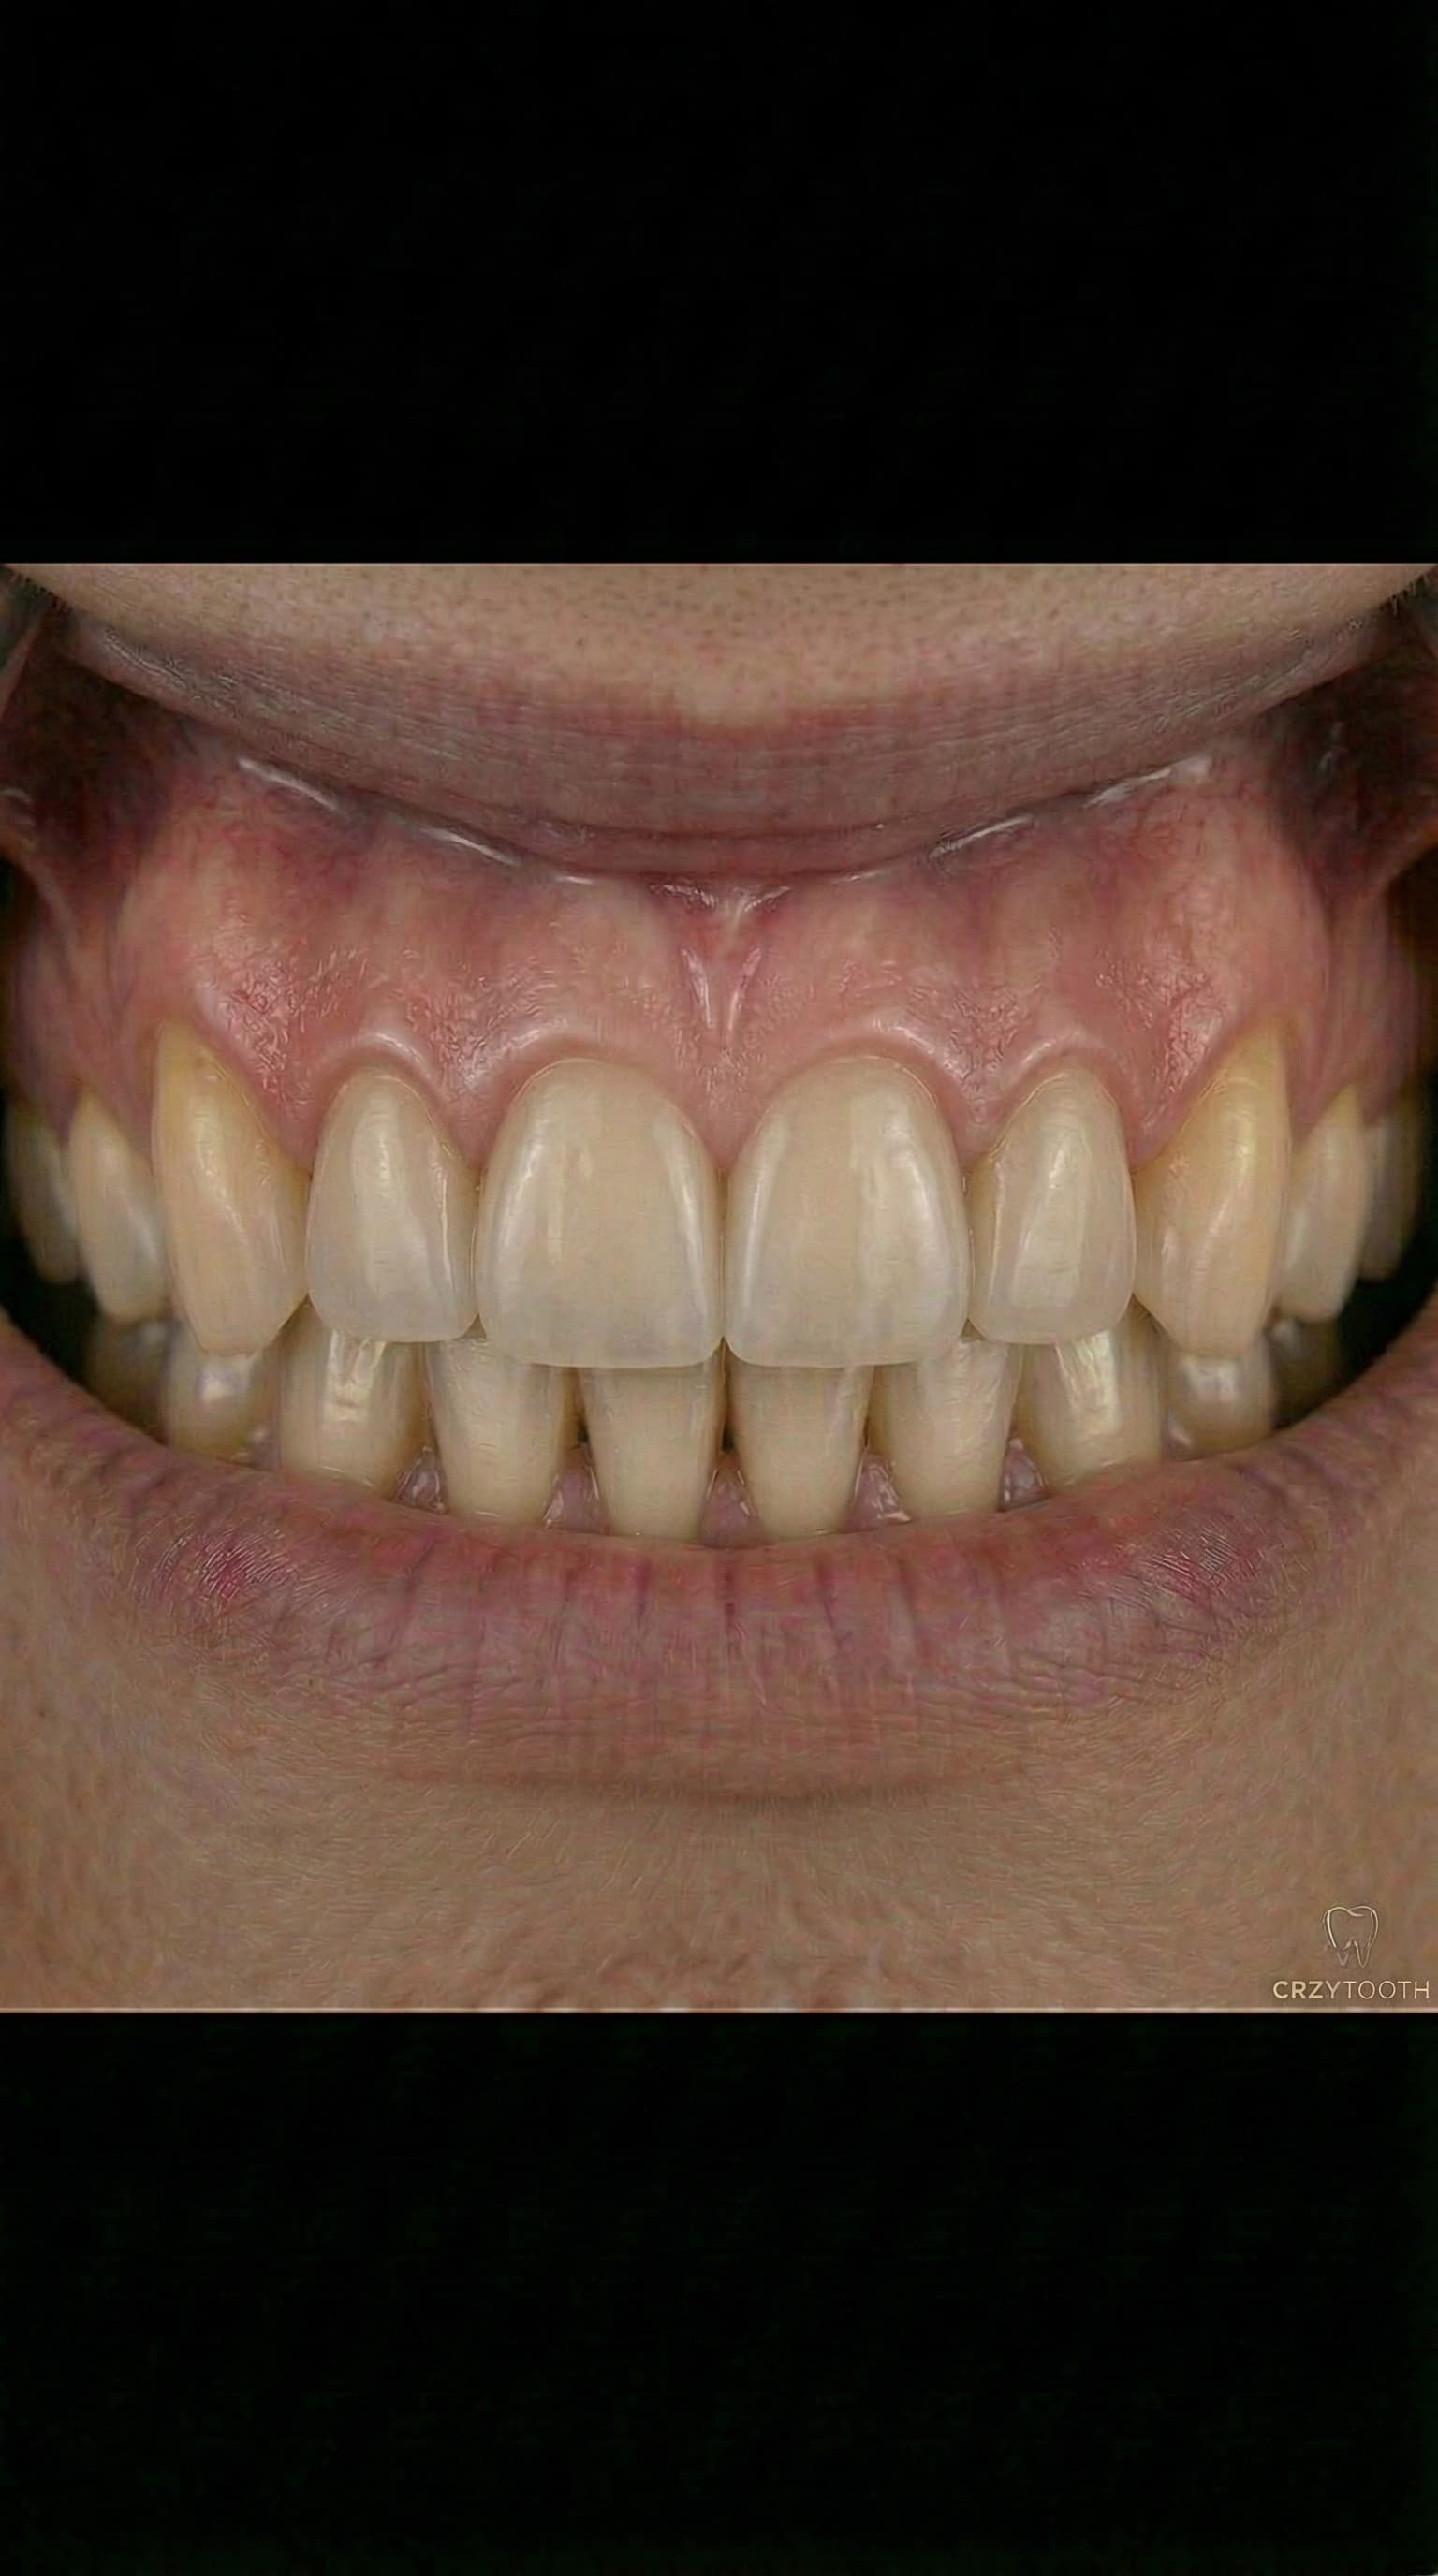

Full Arch Transformation

Watch a complete All-on-4 dental implant journey — from damaged teeth to a brand new smile. Every step performed by Dr. Antipov at our Roseville office.

Permanent Results for Life

Once healing is complete, your permanent prosthesis is placed — custom-crafted from premium zirconia or porcelain. These teeth look, feel, and function like natural teeth. Titanium dental implants are designed to last a lifetime with routine care, and jaw surgery results are permanent. Welcome to your new smile.